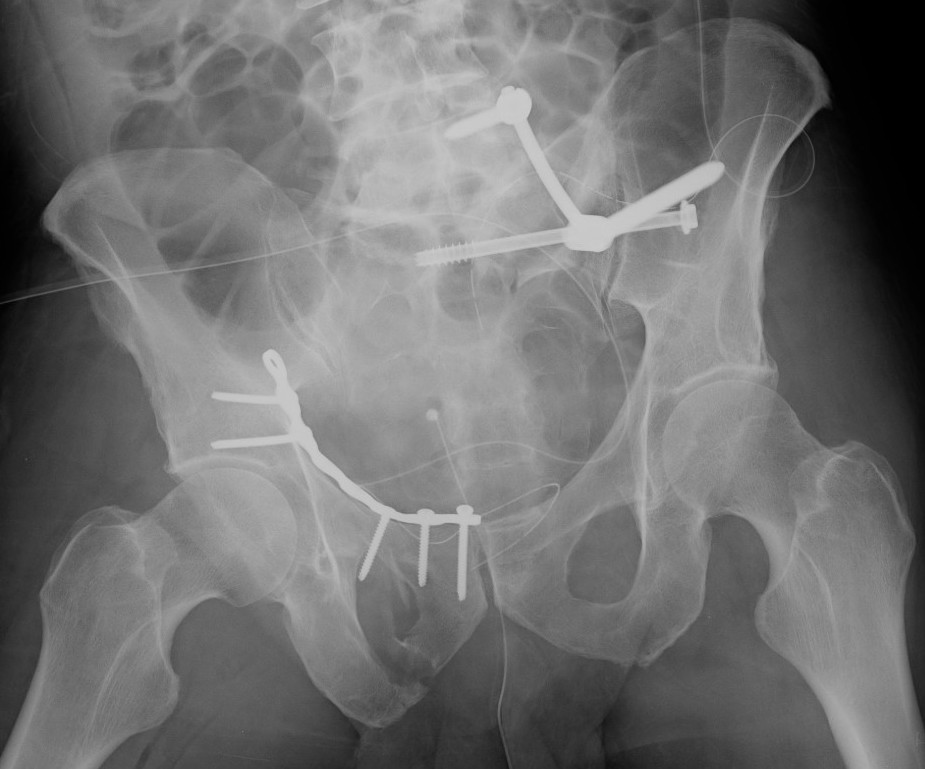

Lumbosacral fixation with SI screw - triangular osteosynthesis

Sacral plate, sacroiliac screws, ramus screws

- sacro-iliac screws

- trans-sacral trans-iliac screws

- trans-iliac posterior tension band plating

- lumbosacral fixation

Anterior stabilisation

Pubic symphysis plates

Percutaneous ramus screws